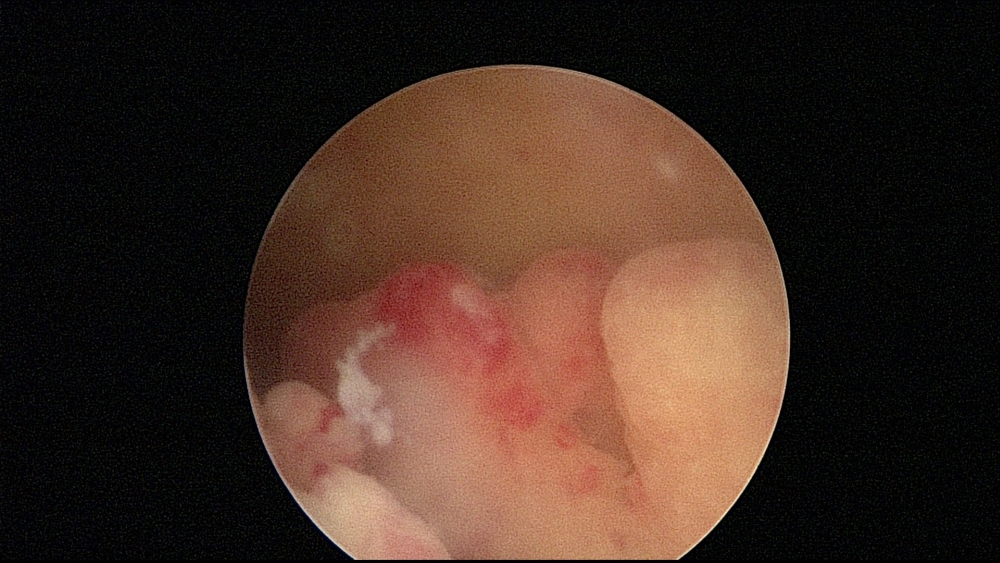

Histeroskopia operacyjna znajduje obecnie zastosowanie w leczeniu następujących patologii macicy:

- mięśniaki podśluzówkowe

- polipy endometrialne